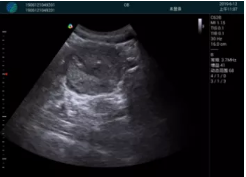

腺體內(nèi)部清晰顯示一低回聲塊影,形態(tài)不規(guī)則,邊界模糊,邊緣呈毛刺狀,內(nèi)部見砂礫樣鈣化

M20引導(dǎo)下穿刺活檢術(shù)